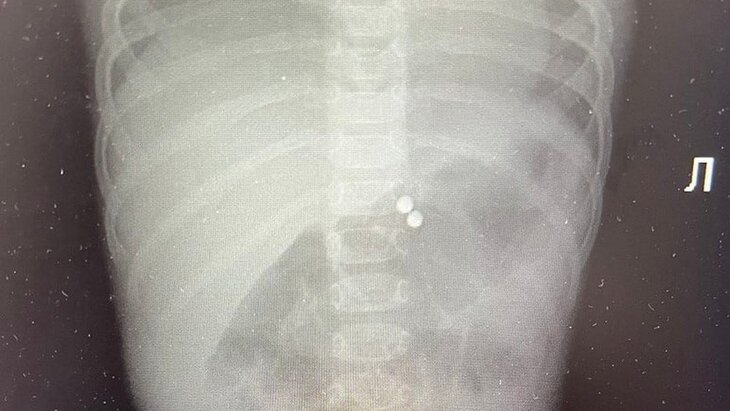

Фото: телеграм-канал "Говорит и показывает Москва"

Через день ребенку стало хуже, ее госпитализировали в детское хирургическое отделение с жалобами на боли в животе и рвоту. Врачи выяснили, что в желудке девочки застряли три магнита, еще один попал в тонкую кишку. В этой связи малышке потребовалась экстренная операция.

"В ходе хирургического вмешательства было выявлено три перфоративных отверстия – соединившись между собой, шарики спровоцировали разрывы стенки желудка и тонкой кишки. Один магнит был извлечен из тонкого кишечника через дефект, который был им вызван, а три – из желудка при помощи специального магнита", – сказал заведующий детским хирургическим отделением Раменской больницы Владимир Хабалов.